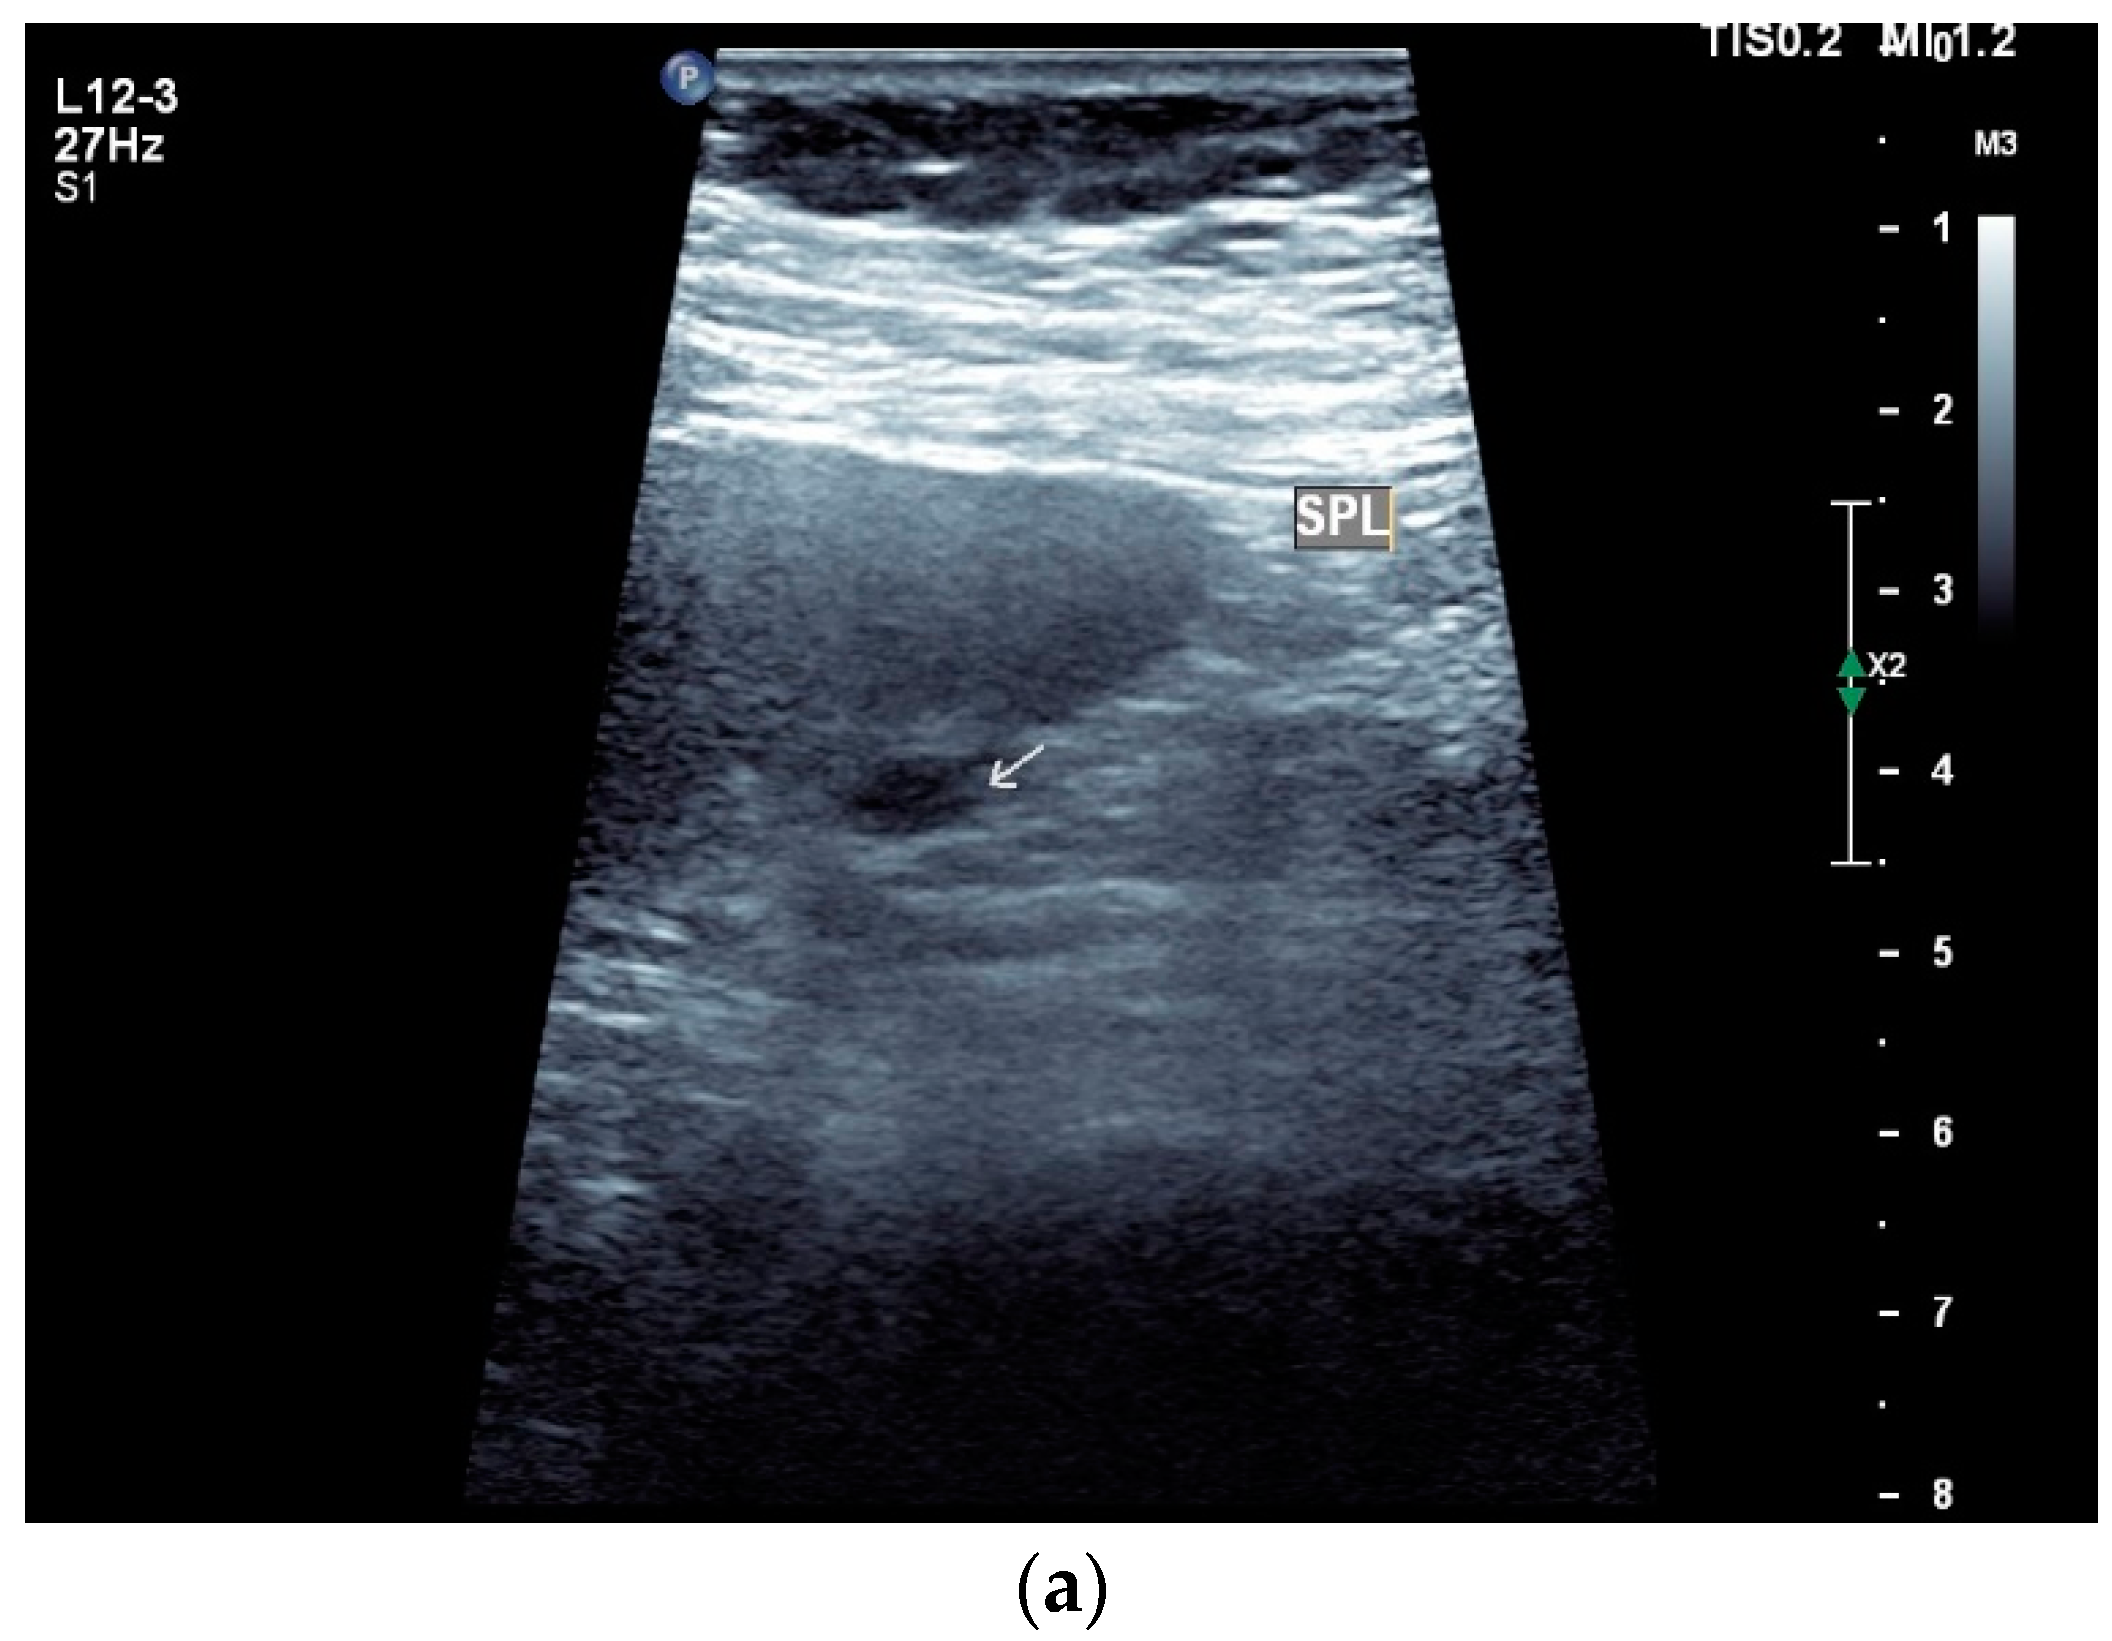

Spleen involvement usually only occurs in disseminated disease. The manifestations are splenomegaly, hypoechoic micronodular (miliary), or macronodular lesions [8,74], as well as splenic abscesses [75] [Figure 4a–d]. In a group of patients with tuberculosis and mostly advanced HIV infection, 37% had splenic lesions [5]. In 33%, splenic lesions were associated with lymphadenopathy, and 16% each had splenic lesions and ascites or splenic lesions, ascites, and lymphadenopathy. Micronodular lesions may be indistinguishable. If this is suspected, examination with a high-resolution linear transducer is recommended. Using CEUS, splenic lesions in the arterial phase showed a hyperenhancement, followed by either a slow washout or a persistent enhancement in the middle and late parenchymal phase [76]. A fast washout was the exception, but nevertheless was also possible. These exceptional cases would therefore be difficult to differentiate from malignancies. There was also rim-like enhancement with central nonenhancement, like abscesses and septation-like enhancement [76]. Another study using CEUS in splenic manifestations of tuberculosis presented homogeneous enhancement (6.7%), heterogeneous enhancement (63.3%), and nonenhancement (30.0%). Most of the cases showed low enhancement. Among these cases, heterogeneous enhancement was divided into septal enhancement type (21.1%) and marginal enhancement type (78.9%) [77] [Figure 4c–g]. The most important differential diagnoses are non-Hodgkin’s lymphoma and other granulomatous inflammations, such as sarcoidosis, especially in the presence of lymphadenopathy. The splenic lesions must be differentiated from mycotic abscesses, leukemic infiltrates, and metastases. In the meta-analysis conducted by van Hoving et al. [78], splenic lesions as manifestations of abdominal tuberculosis had a broad sensitivity of 13–62% in five studies using B-mode ultrasonography. The specificity was higher, at 86–100%.

Figure 4.

Sonographic and CEUS features of splenic tuberculosis. Sonographic and CEUS features of splenic tuberculosis. Subcapsular splenic lesion (arrow) (a), subcapsular splenic lesion using a linear transducer of 12 MHz (arrows) (b). Histologically confirmed tuberculosis from mediastinal lymph nodes. Multiple small splenic lesions (c). Using CEUS with a linear transducer (9 MHz), these are slightly hypoenhanced in the arterial phase (d), and show a progressive washout in the course of the venous phase (arrows) (e). Subcapsular splenic lesion (arrow) with nonenhanced and hypoenhanced parts and hyperenhanced rims indicate a caseous necrosis (f). In another section, an interrupted spleen capsule (arrow) due to a rupture of the caseous necrosis can be assumed (g).